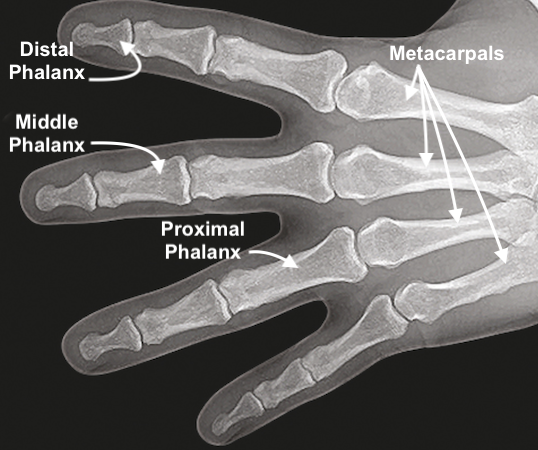

• Normal X-ray Image of distal phalanx, middle phalanx, proximal phalanx, and metacarpals.

Normal X-ray Image of distal phalanx, middle phalanx, proximal phalanx, and metacarpals.